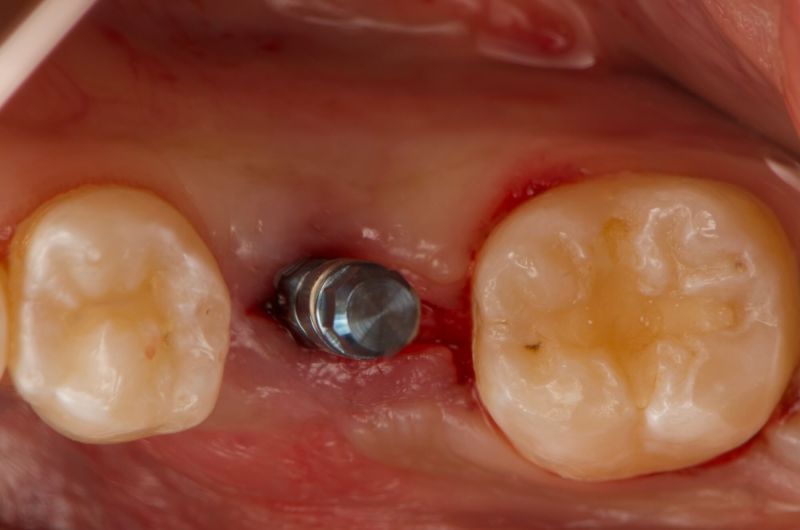

Atraumatic Extraction, Bone Grafting and Implant Placement

Our periodontist removed this damaged tooth and added bone to preserve the area. Four months later, a dental implant was carefully placed followed by a new tooth for optimal chewing and appearance.